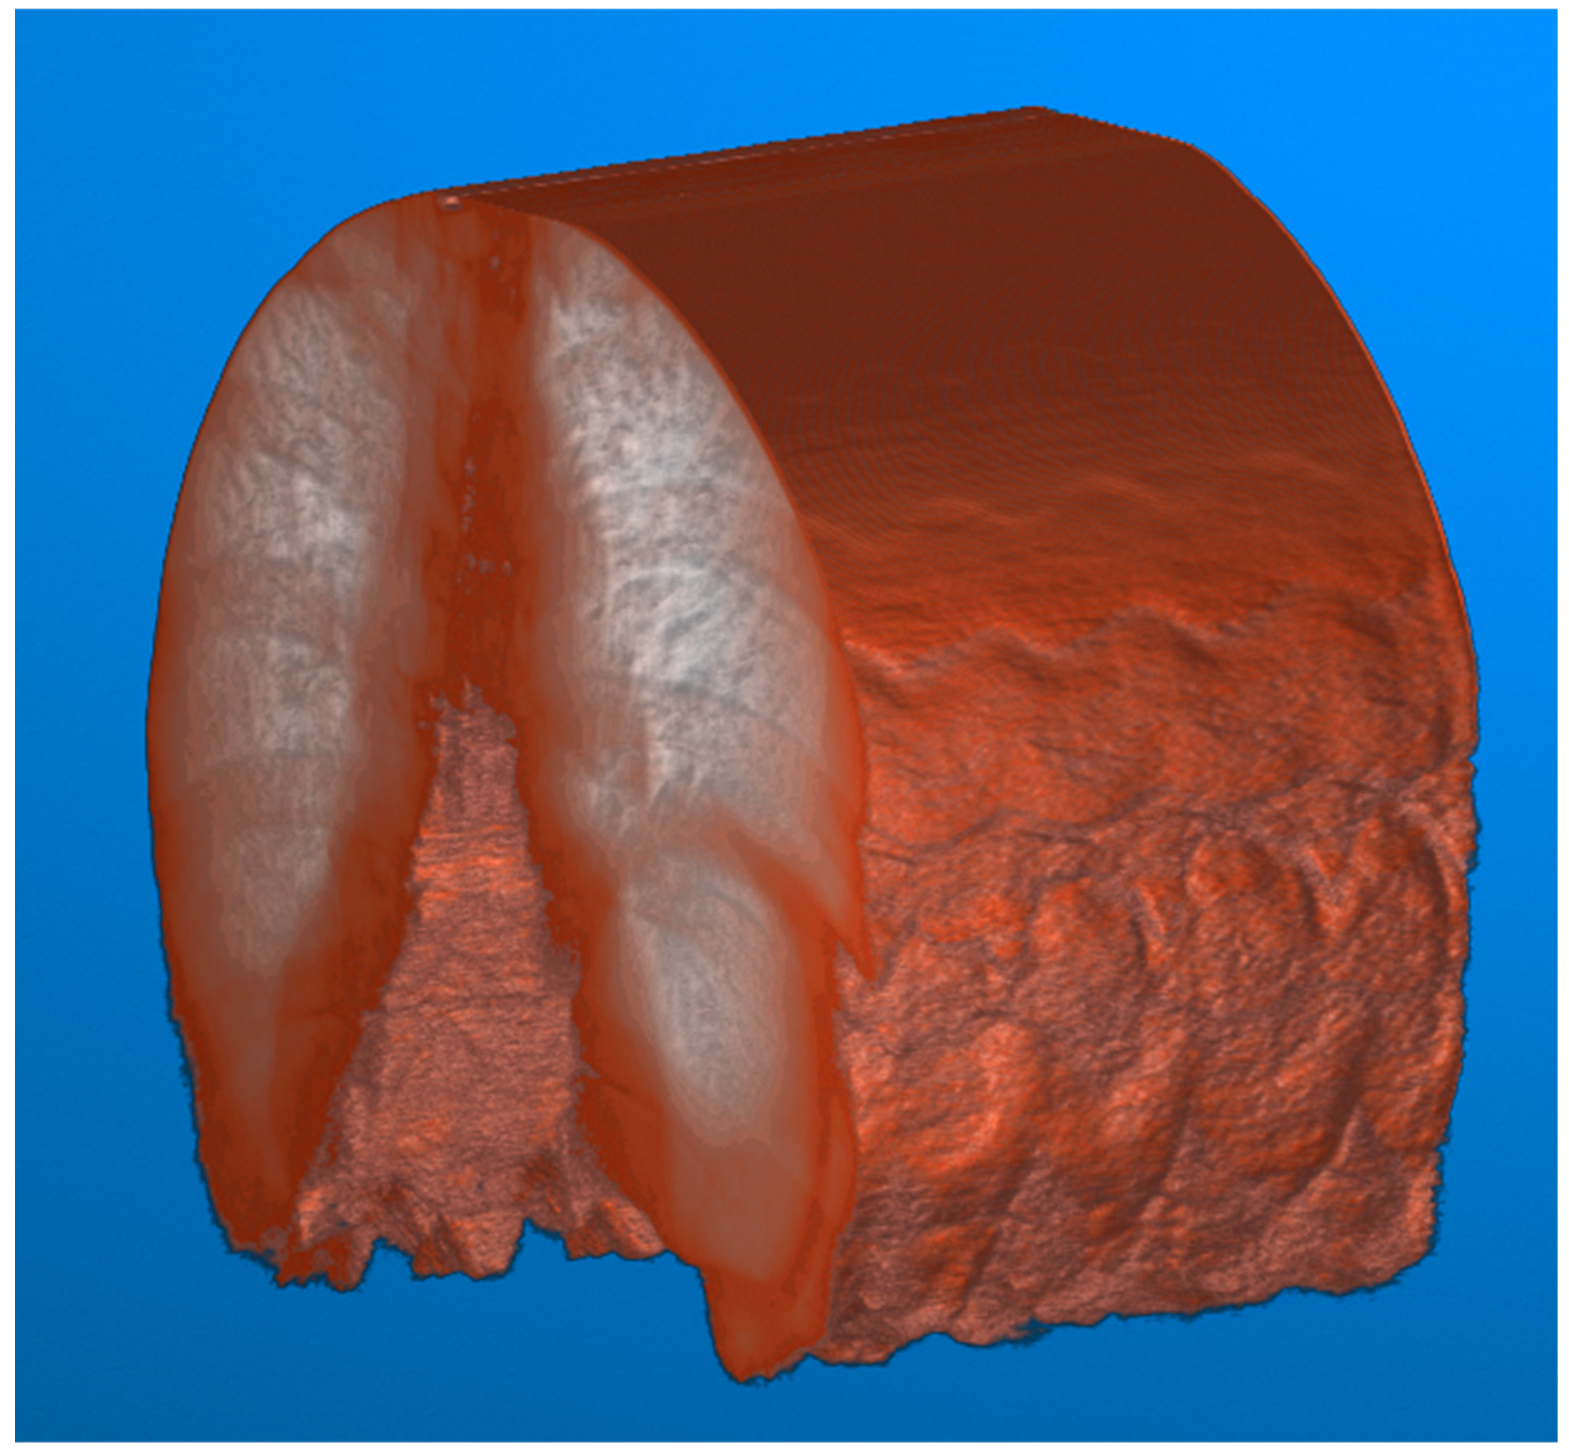

To illustrate the difference between the calibrated and non-calibrated imagery across the range of motion of the diaphragm during normal inspiration, a volumetric approach to image analysis can be taken. The video fluoroscopy imagery can be stacked on the z-axis to form a volume. This volume can subsequently be sliced at a point near the diaphragm along the x-axis to visualize the contraction and relaxation of the muscle.

This visualization (Figure 8) results in a series of troughs representing the inspiration and contraction of the diaphragm and peaks representing the relaxation of the diaphragm. Each video frame of the video fluoroscopy can subsequently be calibrated to visualize the effect of distortion across the range of motion of the diaphragm.

Figure 8. Video fluoroscopy from a case study of chronic left hemidiaphragm elevation [19] during normal inspiration. The resulting video imagery is stacked along the z-axis for a total of 229 frames of images. The image volume can then be visualized, with contrast adjustments applied for improved visualization. The movement of the lungs caused by the diaphragm can subsequently be visualized.